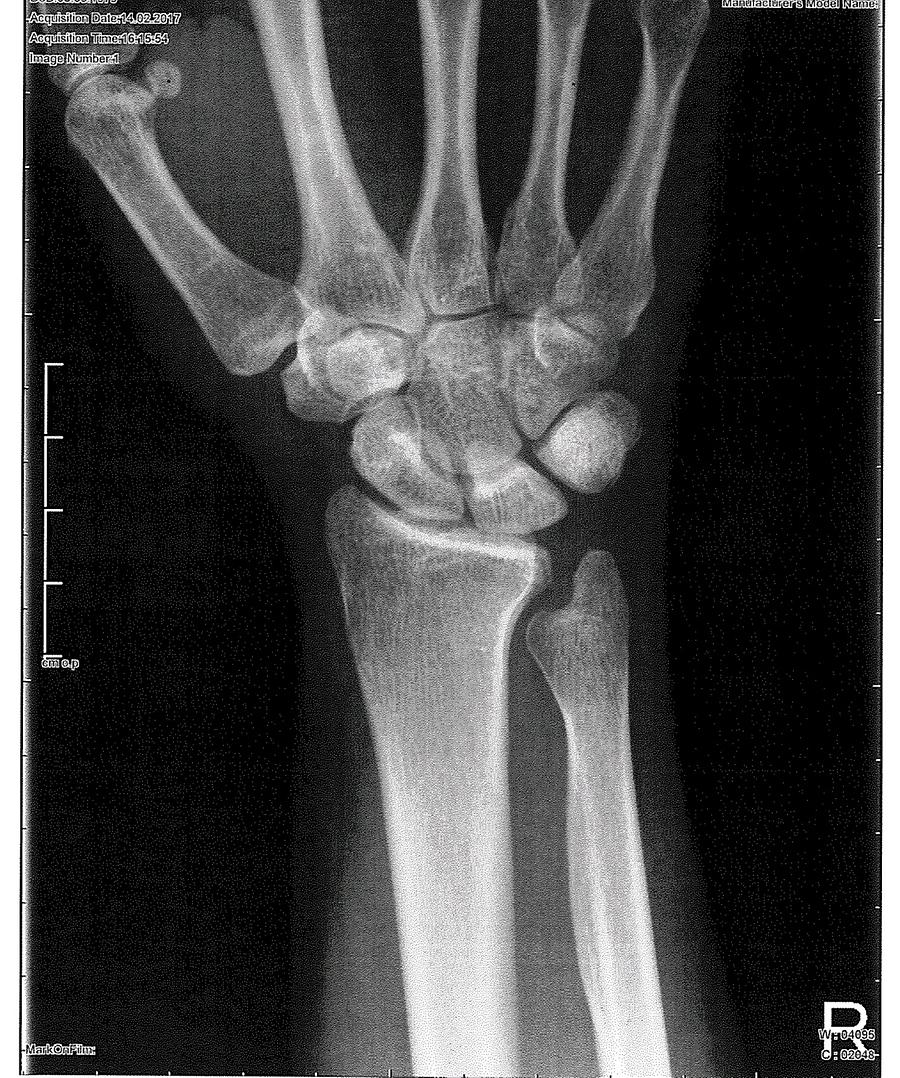

Ich haben eine angeborene ulna minus variante bei beiden Händen. Links habe ich Gott sei Dank noch keine Probleme doch auf der rechten Hand habe ich schon seit vielen Jahren Schmerzen. Bei der rechten Hand hatte ich als Kind auch noch einen Bruch, sodass diese stärker verkürzt ist als die linke. Nachdem ich sehr viele Untersuchungen machen habe lassen, konnte mir erst vor 4 Jahren eine Orthopädin sagen was ich genau habe und wurde auf eine Klinik geschickt die angeblich die Besten seien auf diesem Gebiet. 2 Aufenthalte zu je 3 Wochen kam dann das Ergebnis, dass man für mich nichts machen könne da alles sehr unsicher sei und sie nicht garantieren können, dass ich nach einer OP die Schmerzen einstellen und ich meine Hand wieder vollständig belasten könne. Sie rieten mir bei Bedarf Tabletten zu nehmen (von den ich Haarausfall bekam und die auf meinen Magen gingen) Meinen Job wechseln soll bzw die Stunden reduzieren und meine Familie um Mithilfe bitten solle, wenn es um den Haushalt ginge (leider ist Staubsaugen, Bügeln ja sogar teilweise Wäsche zusammenlegen je nach Schmerzen nicht möglich:-()